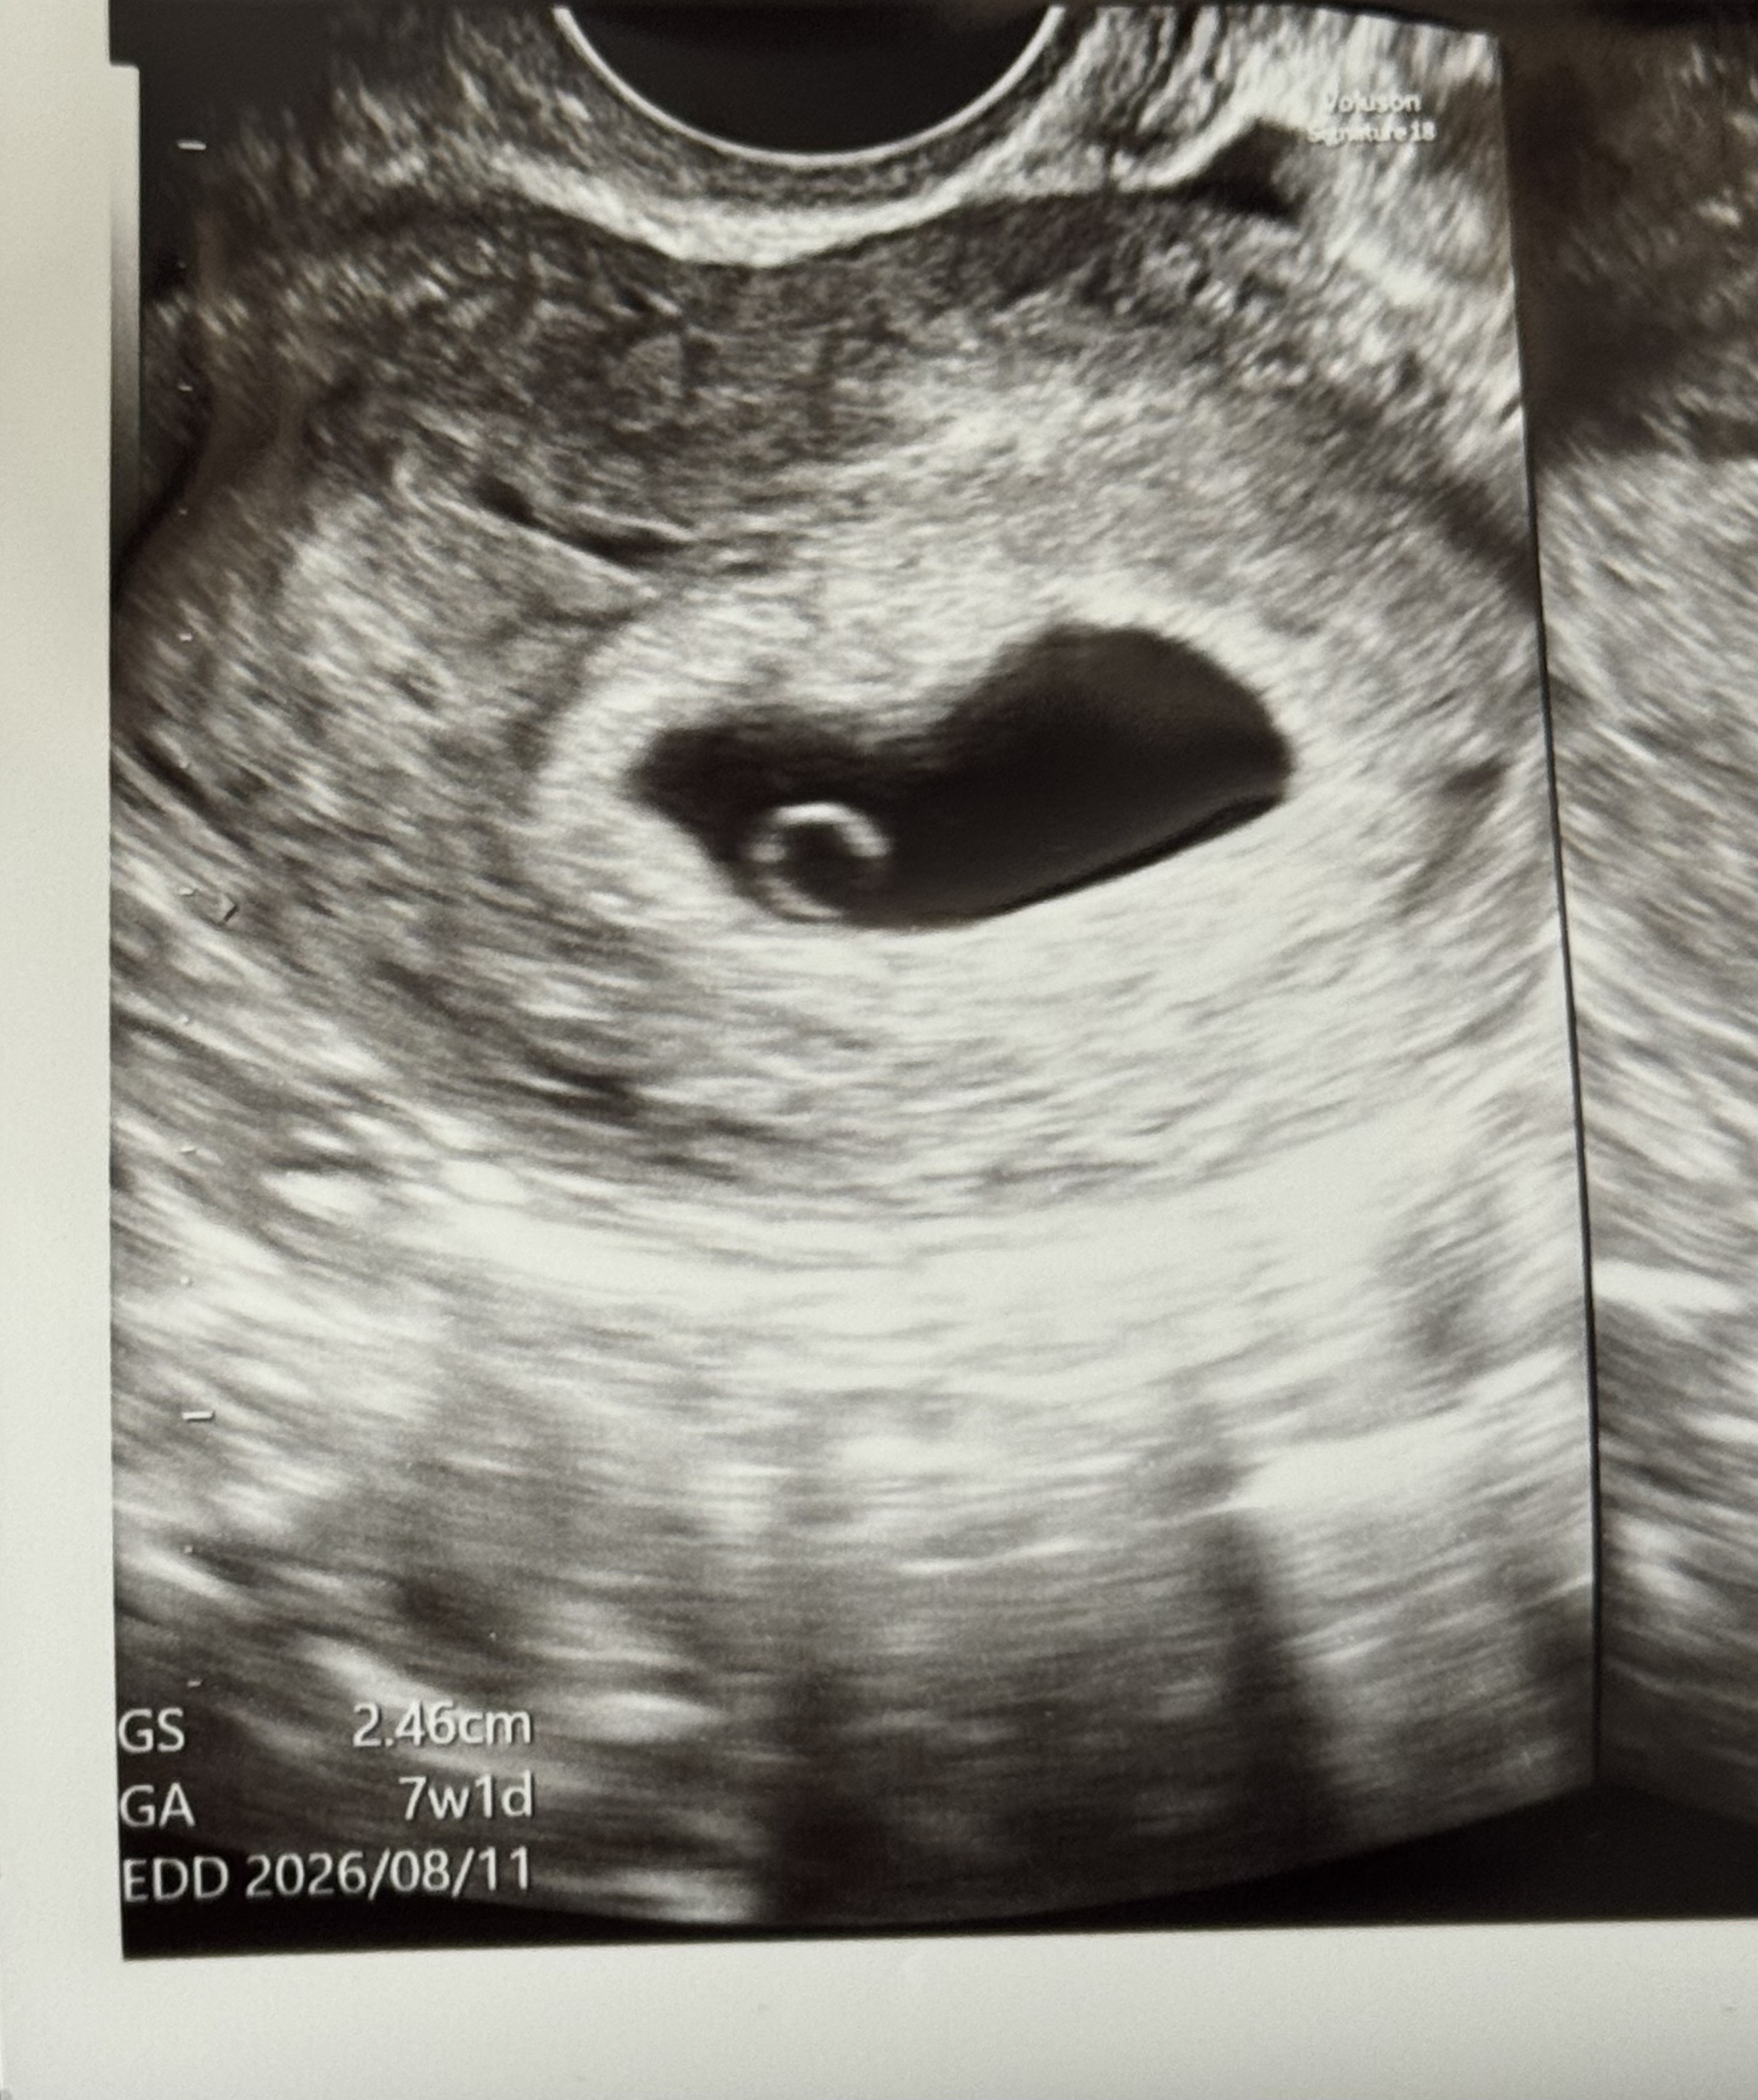

6주0일 아기집1.17cm 난황보고 6주5일 아기집 2.46cm 아기를 못봤어요 ㅠㅠ 당연히 심소들을 수 있을거라 생각하고 갔는데 아기조차 못봤어요.. 저는 작은 왼쪽 점같은게 아기인가 했는데 선생님은 정확하게 아기처럼 보이는게 없다 하시더라구요 ㅠㅠ 저처럼 좀 늦게 심소 들으신분 있으실까요?